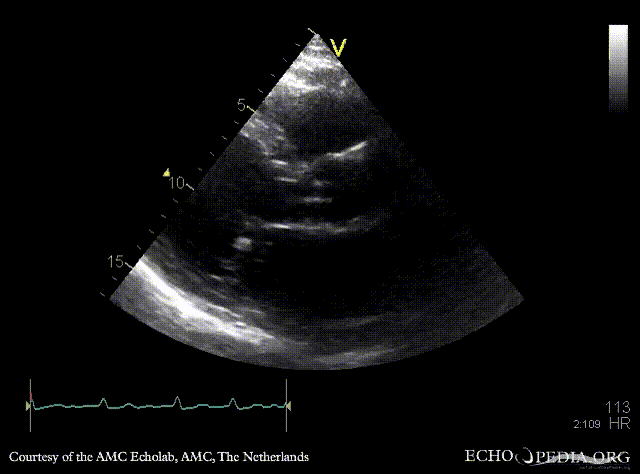

| PLAX: vegetations on PMVL | A4CH |